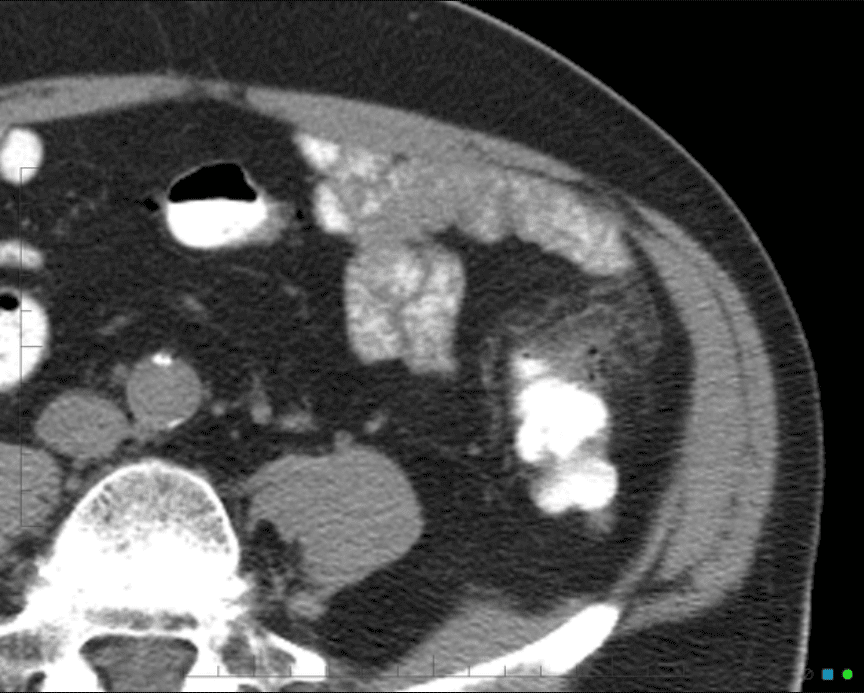

Viêm túi thừa

Viêm túi thừa - Ảnh 2

» Thông tin: Nam giới – 25 tuổi.

» Lâm sàng: Đau hố chậu trái.